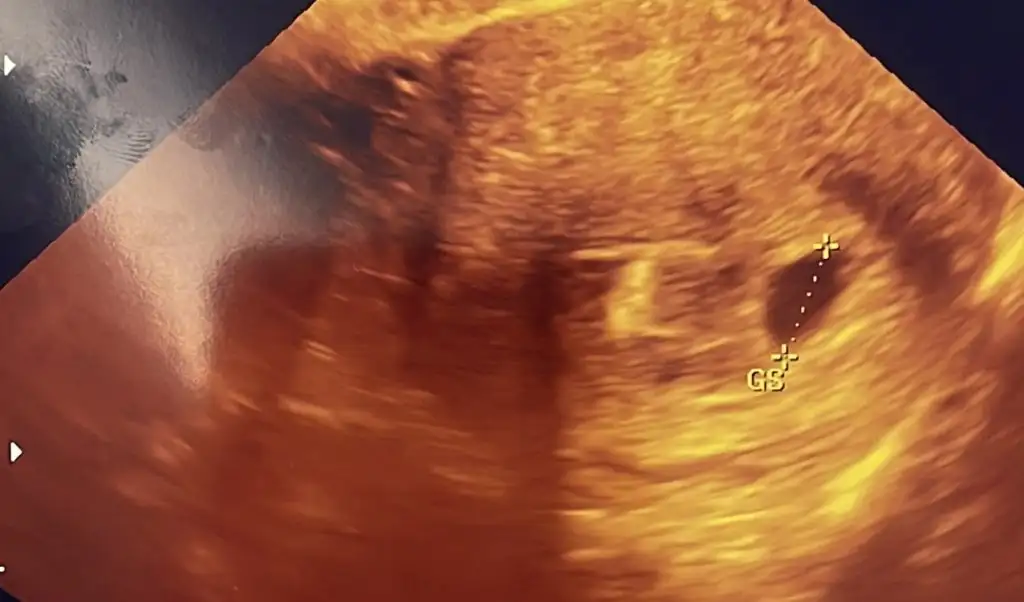

Şöyle çıktısı canm

Benimde siyah beyaz olan 5. Haftamın ultrasonu. Renkli olan dün acilde doktorun çektiği ultrason yani 7. Hafta. Kesede büyüme var ama yolk saçını görmedi. Çok huzursuz oldum.